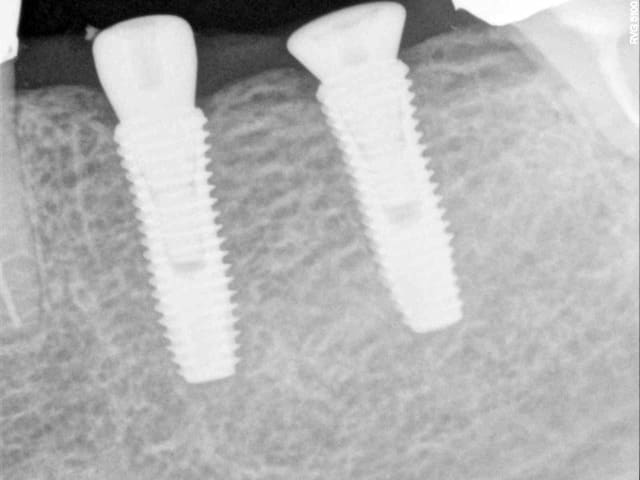

voici 2 implants de 4 mm de diamètre posés en 1 temps avec des piliers de cicatrisation de diamètre différents et pourtant une même conservation du niveau osseux

Dentium 4 mm diam tre qeeqia - Eugenol